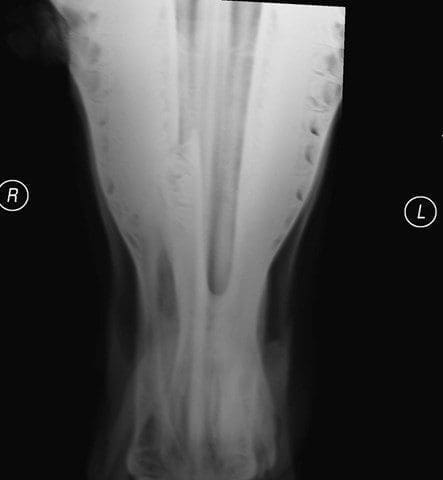

The above horse was first seen in the March for a wound on his right mandible, facial swelling, and an inability to eat. Radiographs showed a unilateral displaced fracture of the right mandibular body between the first and second cheek teeth. There was a 4 cm x 2 cm foul smelling wound on his right lateral mandible in the region of the fracture.

An external fixator consisting of four bone pins passed through the mandible bilaterally was applied. Two pins were on either side of the fracture. The fixator consisted of three 4 mm pins and one 5mm pin. The 5mm pin was the third pin caudally and could only be inserted through the right ramus and just into the left ramus but without passing completely through the ramus. Fracture reduction was confirmed and the pins were cut with bolt cutters 4 cm from the skin. Two lengths of tubing (a disused nasogastric tube) were cut to a length that would span all the pins with 2cm more at either end. The ends were plugged with swabs and then the tubing filled with Technovit. Once the Technovit had cured, the fracture reduction forceps were removed and the fracture was held firmly in reduction. The ventral incision was closed with 2-0 PDS in the SQ and 0 Prolene in the skin. A 2cm area in the middle of the incision was left open for drainage. The wound on the face was gently debrided with a Volkmann spoon. The pin/skin interfaces were covered with swabs soaked in intramammary antibiotics. Radiographs were taken on numerous occasions and were inconclusive with regard to tooth root involvement.